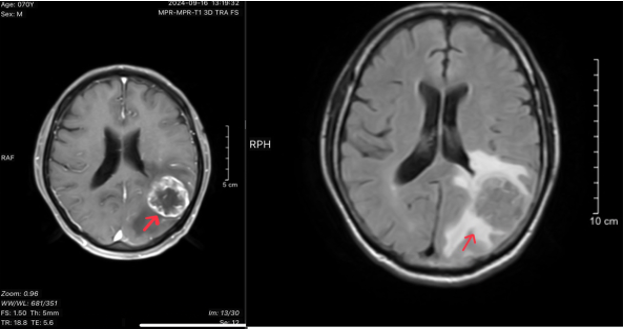

- MRI não:

- Hình 2: Hình ảnh cộng hưởng từ não cho thấy nhu mô bán cầu tiểu não trái, thùy thái dương trái, thùy đỉnh trái có các nốt và khối, khối lớn kích thước 35x36mm, tín hiệu tổ chức, bờ không đều, ngấm thuốc viền sau tiêm, phù não xung quanh.